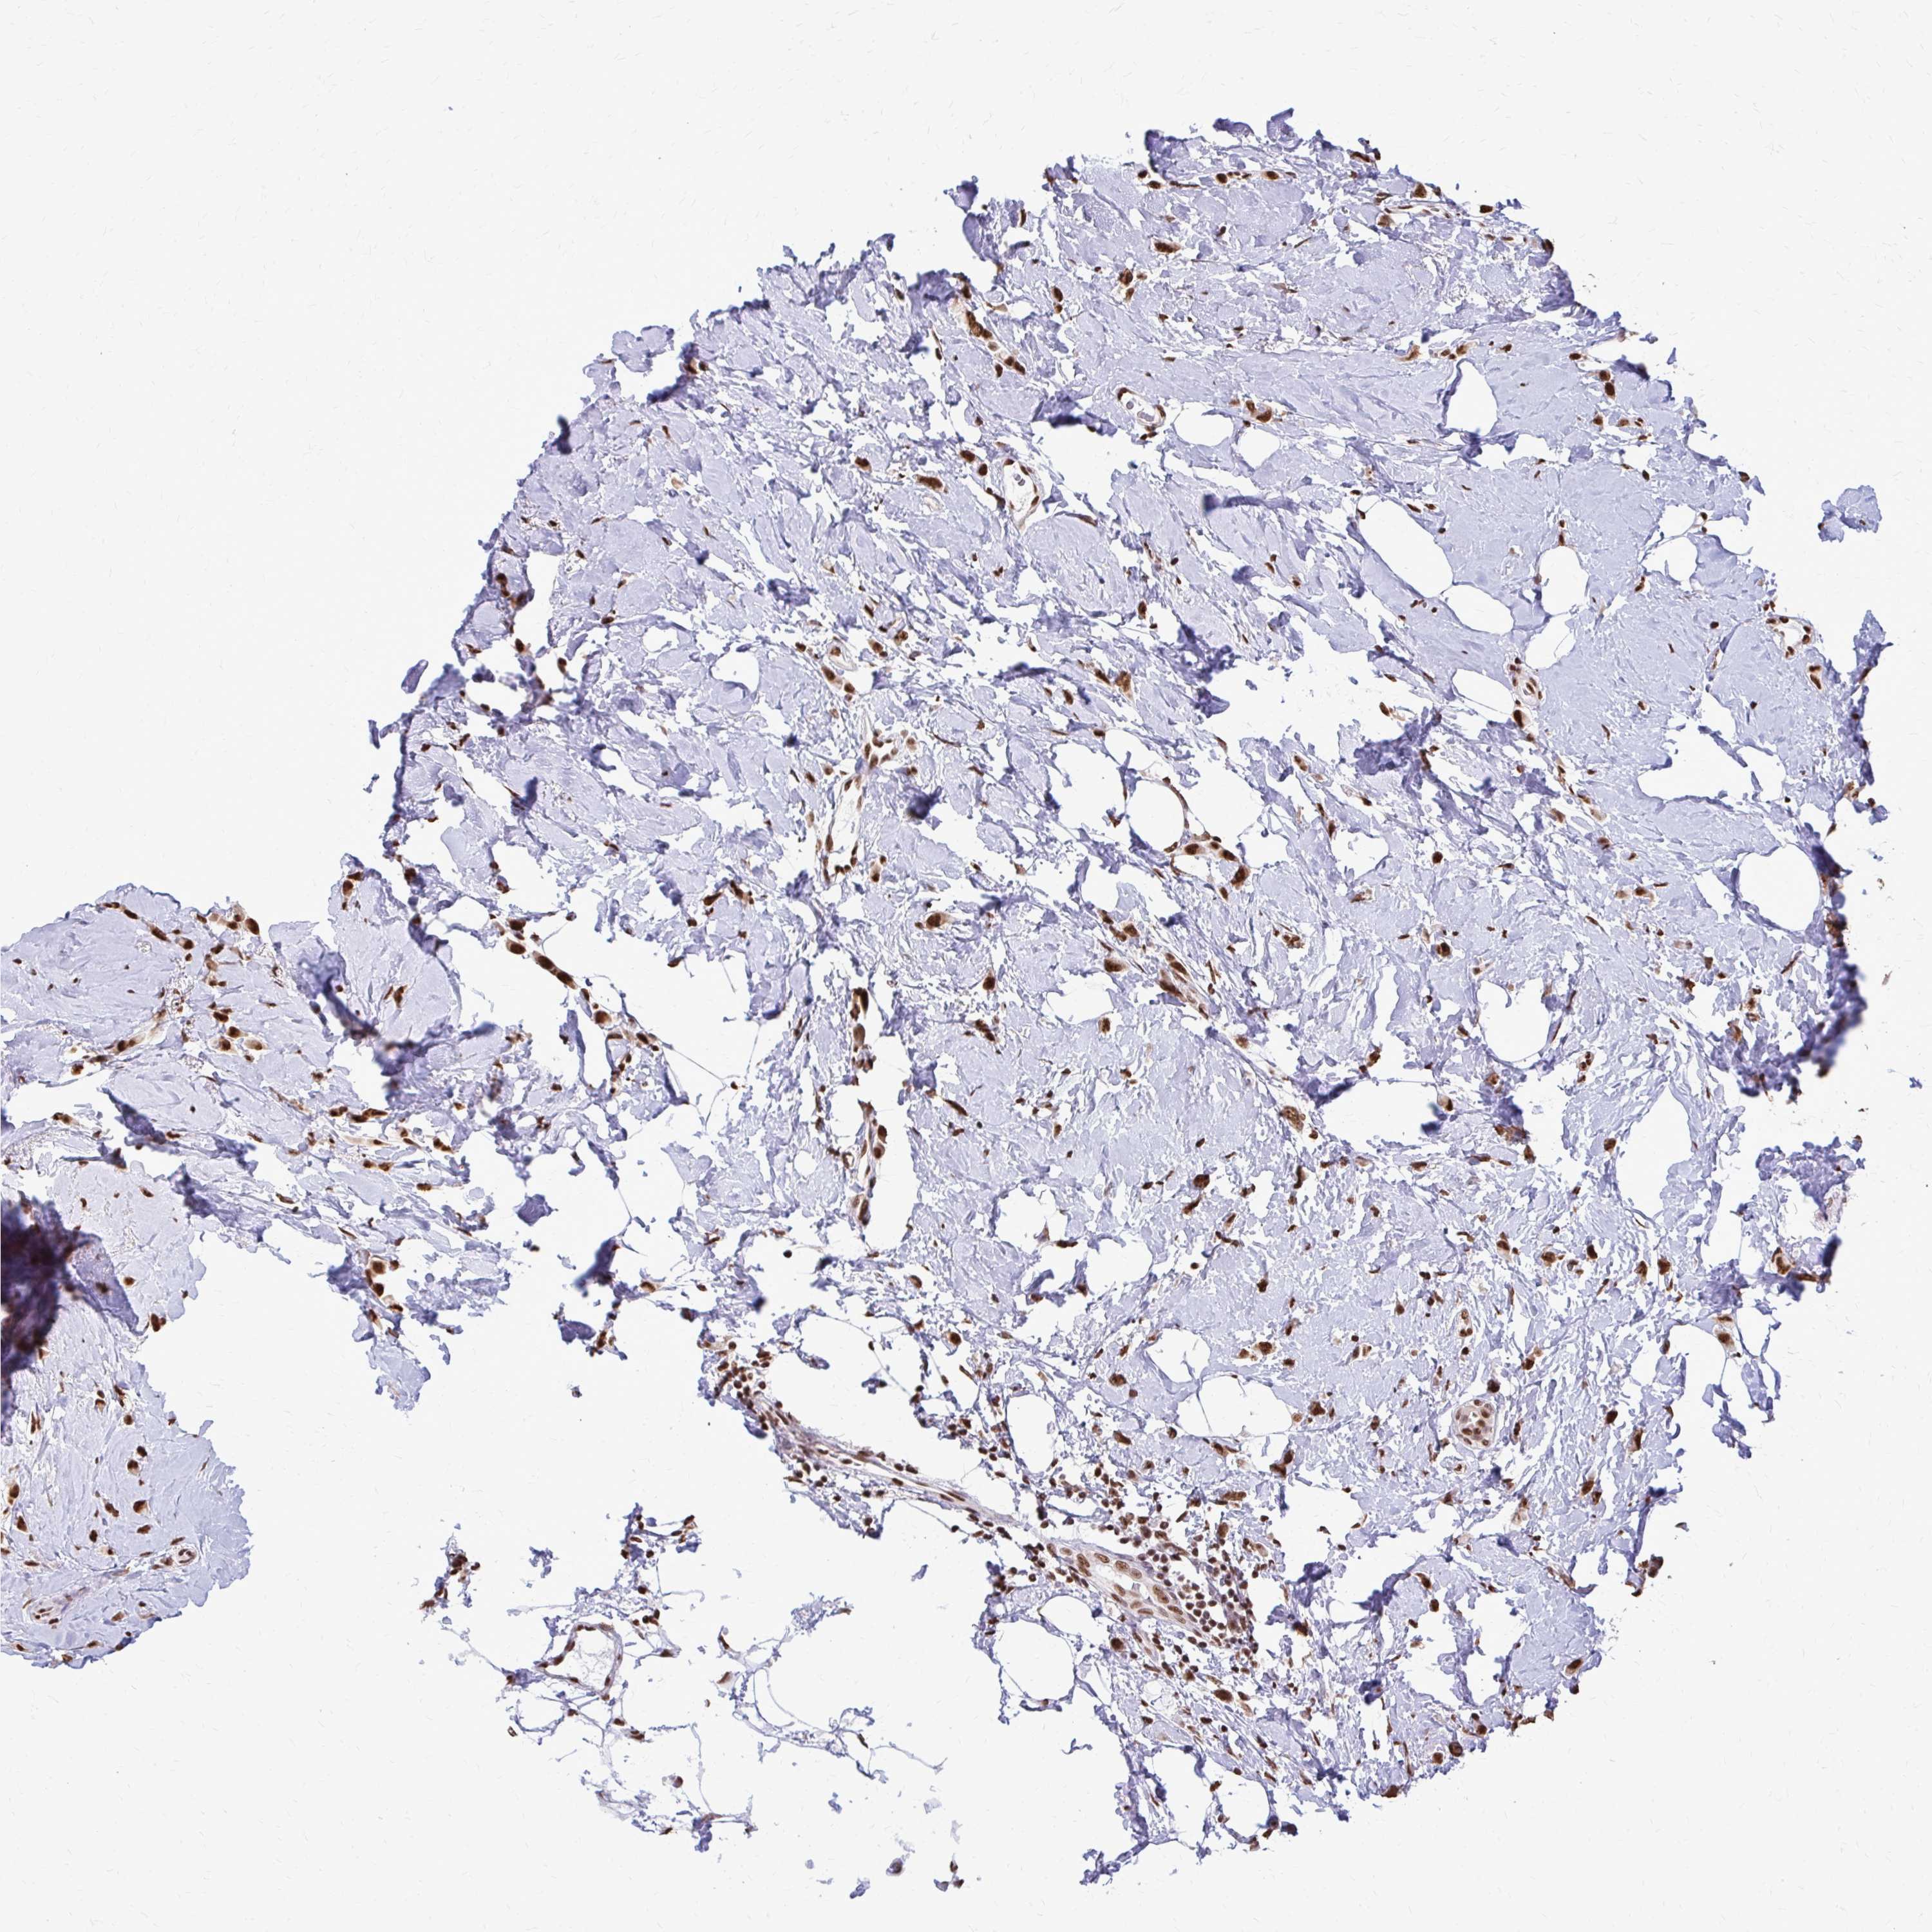

CANCER BREAST CANCER Show tissue menu

BRCA TCGA BRCA VALIDATION PROTEIN EXPRESSION

Breast cancer

Human cancer